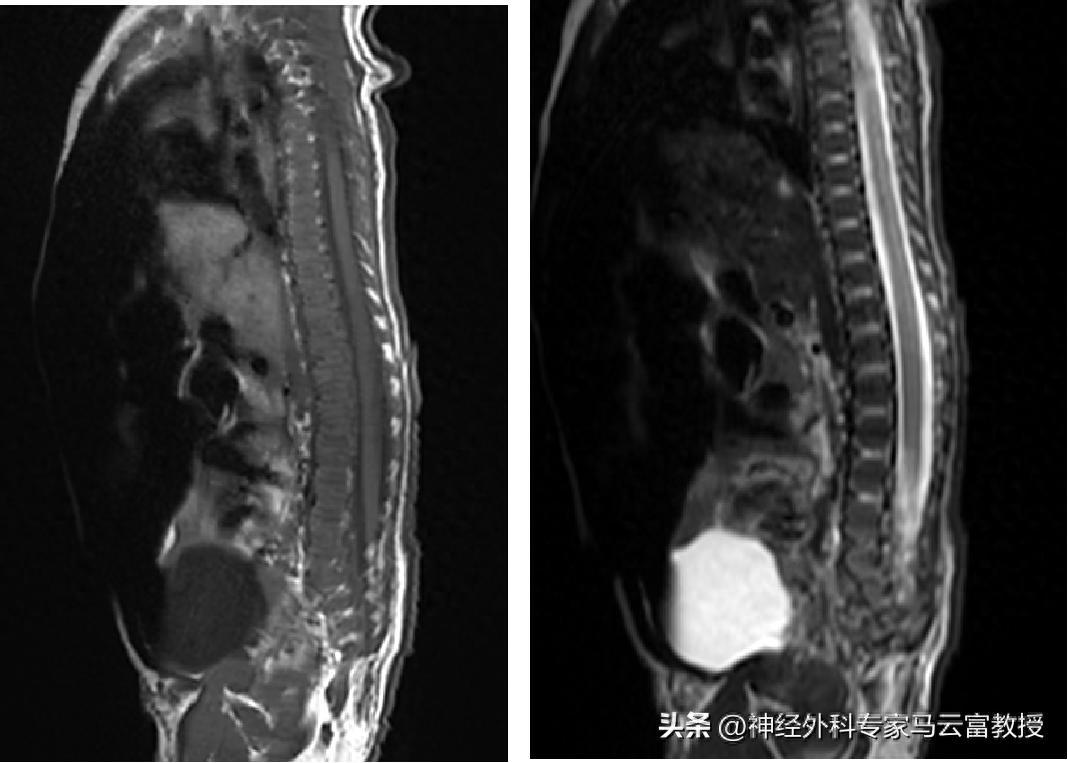

腰骶椎MRI顯示脊髓栓系+脊髓脊膜膨出

脊髓脊膜膨出是脊柱裂的典型表現,因寶寶脊柱椎板先天未正常融合,脊髓和脊膜會從脊柱缺損處向外膨出,形成體表可見的包塊;椎管內脂肪瘤則是椎管內長出的異常脂肪組織,會牽拉、壓迫脊髓;而脊髓栓系綜合徵,正是因脂肪瘤、膨出的脊膜等組織持續牽拉脊髓,使其無法隨寶寶身體發育正常上移,進而持續損傷神經功能,三者常合併出現,相互影響加重病情

脊髓脊膜膨出的典型症狀在新生兒期就十分明顯,最突出的是腰骶部出現大小不一的囊性包塊,哭鬧、用力時包塊會膨隆變大,部分包塊表面還會伴隨皮膚髮紅、色素沉着、異常贅生物或毛髮增生;同時因脊膜和脊髓膨出壓迫神經,寶寶還可能出現餵養困難、腹脹、大小便排泄異常,部分寶寶會伴隨肢體活動無力、肌張力異常等神經受損表現,若包塊破損還可能引發腦脊液漏、顱內感染等嚴重併發症。